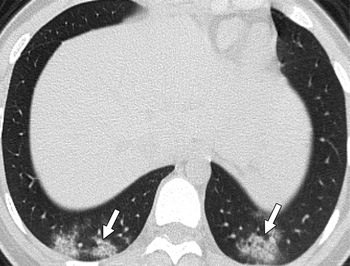

Research shows 77 percent of children who are confirmed positive for the virus have no findings via chest CT.